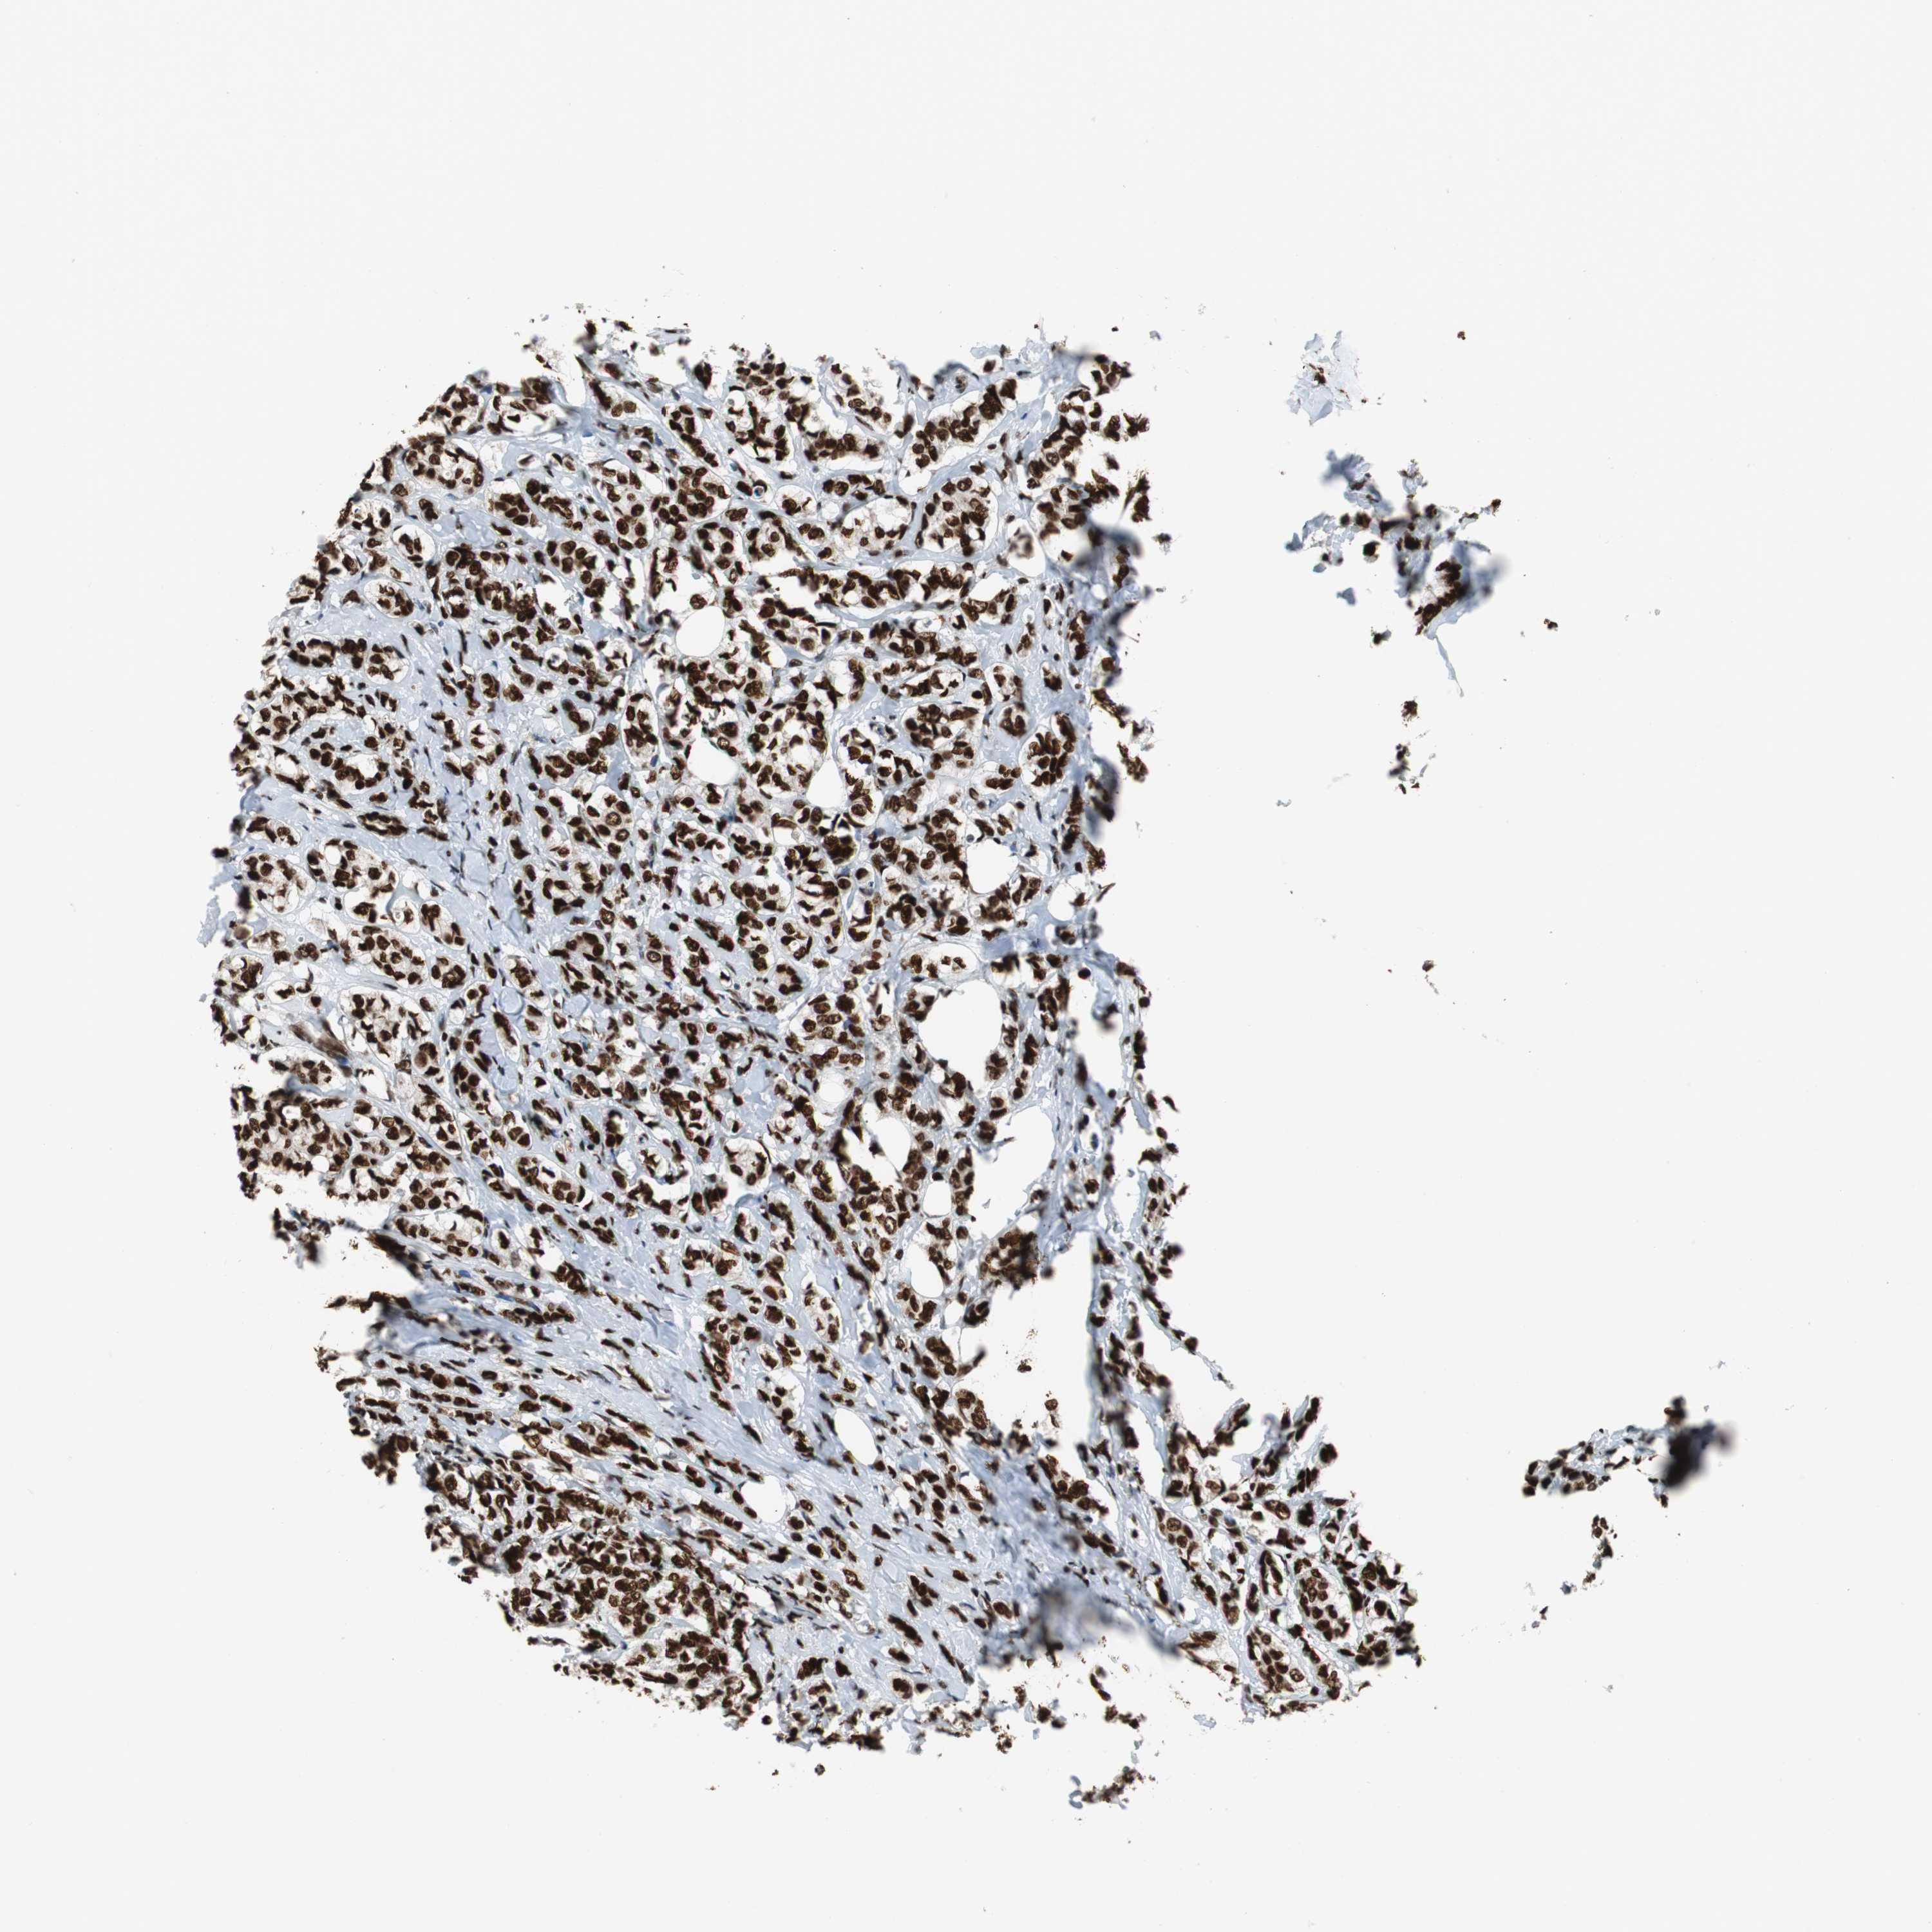

HDAC1

CANCER BREAST CANCER Show tissue menu

BRCA TCGA BRCA VALIDATION PROTEIN EXPRESSION